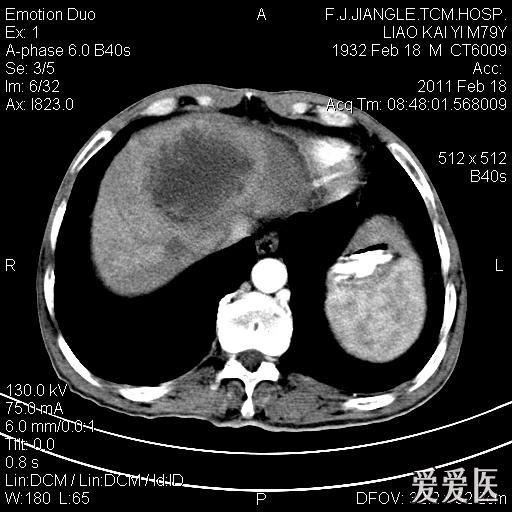

一例确诊的肝脓肿ct平扫增强

图片尺寸512x512